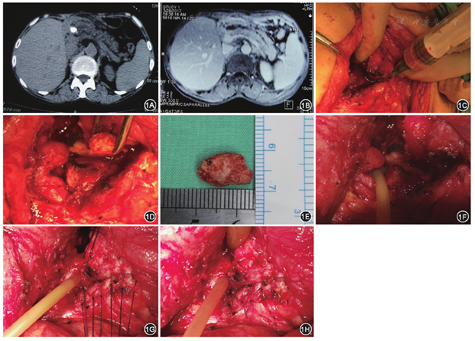

患者2017年4月3日在全身麻醉下接受胰肠吻合口拆除重建,胰管取石术。术中沿原切口切开入腹,皮下腹壁各层组织水肿,切口下粘连极重,组织间致密粘连、无明显间隙。仔细分离粘连,显露结肠上区胰肠吻合口和部分胃,见腹腔组织广泛水肿,胰腺质地硬、肥厚肿胀明显。胃后和胰肠吻合口周围可及包块、质硬、界限不清,分离过程中破入肿块内部,有脓液流出(图1C),留取部分脓液行细菌培养。顺势分离,进入胰肠吻合口,见吻合口狭窄,吻合口处胰腺质地硬,反复探查无法探及结石。在术中超声引导下探及胰管结石,以10 ml注射器穿刺定位胰管结石,于胰腺表面沿胰腺长轴剖开胰腺直至胰管,见胰管内近胰肠吻合口处有1枚结石,大小约1.5 cm×0.9 cm(图1D,图1E),取出结石,切除胰肠吻合口处部分胰腺组织。术中病理学检查结果:慢性炎症。于胰肠吻合口处置入16号T管,短臂适当修剪后一端置入空肠襻,一端置入胰管内(图1F),长臂经胰肠吻合口引出,缝合剖开胰腺组织,缝合胰肠吻合口,重建胰肠吻合(图1G)。局部冲洗,于胰肠吻合口旁的脓腔内置1根引流管(图1H),将引流管及T管长臂分别自腹壁引出。